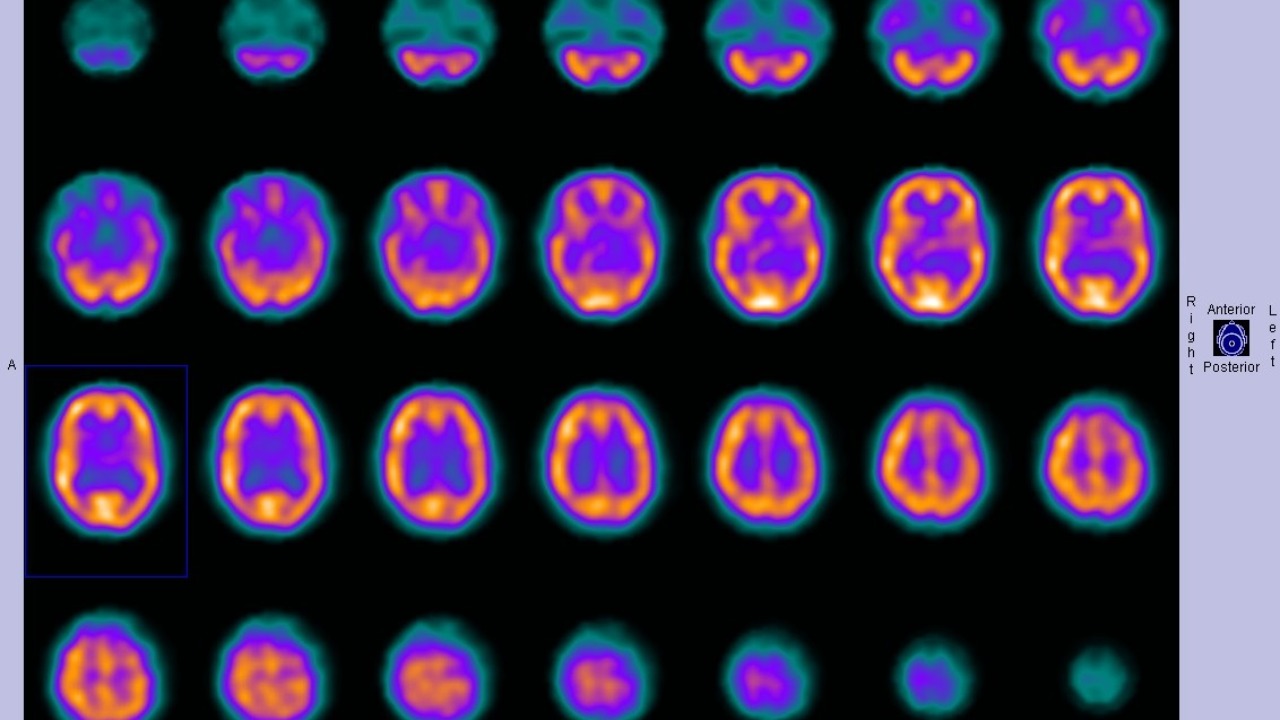

The latest studies go beyond broad hints of diversity and describe a specific, previously unrecognized four-layer organization inside the hippocampal CA1 region. Instead of a single band of pyramidal neurons, scientists now see a stack of distinct cellular strata, each with its own gene expression profile and likely its own role in processing experience. This layered pattern was not obvious under a standard microscope, which is why it escaped notice for so long, but it emerges clearly when researchers combine high-resolution imaging with molecular tools that label different cell types.

By visualizing gene RNA across CA1, the team could separate neurons into four discrete groups that line up in space, revealing a hidden architecture that reshapes how learning and recall are understood in this part of the brain. The work shows that what once looked like a single homogeneous subregion is in fact a finely partitioned structure, and that each layer may be differently affected by disease. The finding, described as a hidden four-layer structure in the brain’s key memory hub, gives researchers a new anatomical framework for asking why some memories are more fragile than others.

Peeling back the hippocampus’s internal structure required a combination of techniques that go far beyond standard histology. Researchers used high-throughput gene expression mapping to label neurons according to the RNA they produce, then overlaid those molecular fingerprints on precise anatomical coordinates. That approach turned a seemingly uniform sheet of cells into a mosaic of distinct populations, each clustering into one of four spatially ordered layers. The result is a kind of molecular topography that reveals boundaries invisible to the naked eye.

The work is part of a broader effort to build a cellular atlas of the brain’s memory center, integrating transcriptomic data with connectivity and physiology. In reports describing how a USC study reveals hidden cellular layers in the hippocampus, scientists outline how they combined gene profiling with advanced imaging to separate overlapping cell types. By aligning those data with known input and output pathways, they can start to infer how each layer participates in the flow of information, and which ones might be critical nodes where disruption leads to memory failure.